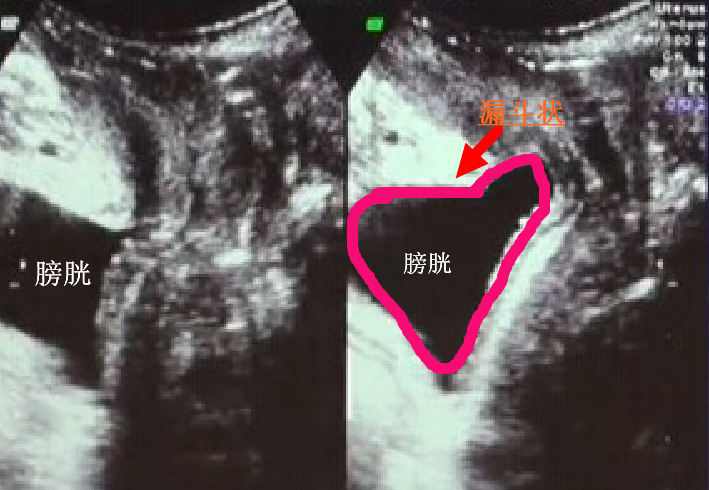

1.尿道漏斗形:指静息状态下和最大Valsalva动作时尿道倾斜角的差值。

尿道漏斗形